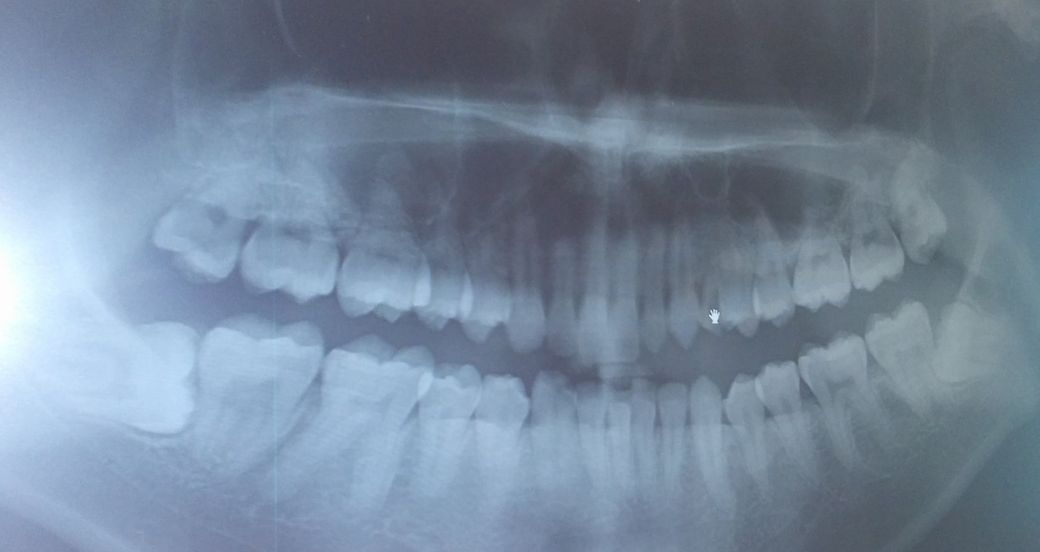

2015년 엑스레이 사진, 그리고 현재 2022년에 찍은 상악 1개 사진과 하악 2개 사진이에요.

2015년이면 20대 후반이고 지금은 30대네요..

이거는 제가 알기로는 저 어릴 때부터 안 뽑고 계속 가져왔던 것 같아요. 유치라고 하나요? 그래서인지 상악 치아 총 갯수가 홀수개에요.

- 하악에 사랑니

엑스레이로는 사랑니 둘 다 보여야하는데 막상 찍으니 사랑니 하나는 안 보이고 하나는 이미 썩어서 아주 그냥 치아에 호수가 형성되었네요..

그리고 전체적으로 입 안 깊이 갈수록 잘 안 보이는 치아일수록 상태가 안 좋은 것 같아요.

현재 20번대 송곳니 뒤쪽으로 유치 송곳니가 남은것으로 보입니다. 해당치아가 충치가 심해서, 발치해야할 가능성이 높습니다.

만약 살릴 수 있다면, 신경치료, 포스트를 하여 살리는게 좋을 것으로 보입니다. 현재 치아가 한개 더 많은데, 이 상태로 치열이 배열되었기 때문에, 만약 이 치아를 발치한다면 교정을 하거나 임플란트를 해야하기 때문입니다.

사랑니는 충치가 심하여 발치가 필요해보입니다. 치과에서 검사를 받아보시기 바랍니다. 감사합니다.